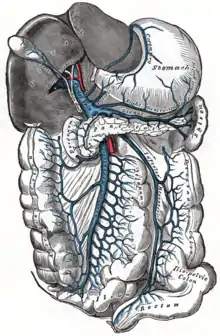

Splanchnic Circulation

This includes the blood supply and drainage - via the portal system - of the gut as well as the pancreas, liver and spleen. The liver is drained by the hepatic vein.

Hepatic Portal System

All the blood from the GI system below the esophagus drains into the hepatic portal vein. The portal system also drains the spleen and pancreas. Blood is conveyed to the liver for processing where it passes through millions of liver sinusoids. This allows the reticuloendothelial cells that line the sinusoids to remove bacteria and other particulate matter. Blood finally leaves the liver via the hepatic vein where it drains into the inferior vena cava.

The total blood flow to the liver is about 1.5 liters per minute, of which two-thirds is carried by the portal vein. The blood in the portal vein is more oxygen-saturated than blood in the systemic venous system; it is about 80-90% saturated and provides about 70% of the oxygen requirements of the liver.